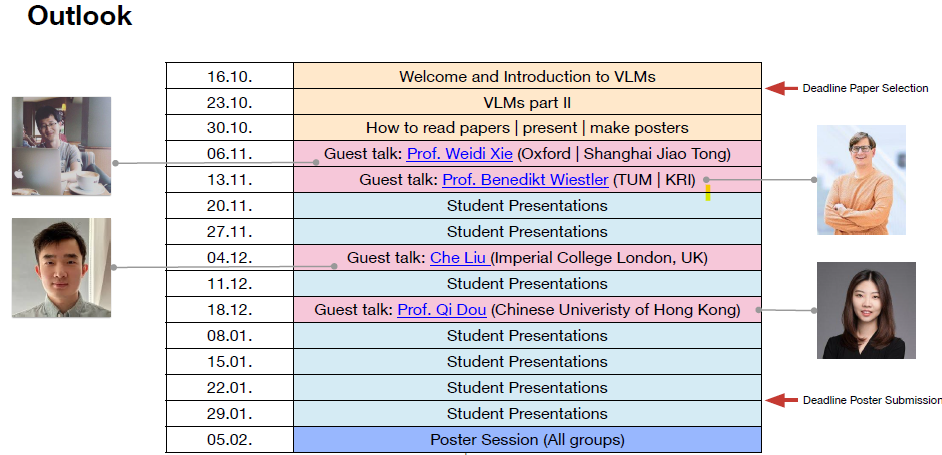

[09.2023] My seminar 📘 AI for Vision-Language Pre-training in Medical Imaging (IN2107) is now open! For more details, please visit the course GitHub repository.

- (S 24/25) Master seminar, Technical University of Munich.

- Course ID: IN2107.